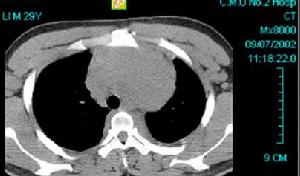

(三)心臟X線表現 酷似二尖瓣病變的表現,兩肺野鬱血,心界呈輕度到中度增大,主要表現為左心房和右心室擴大,食管鋇餐檢查可見到食管輕度到中度的壓跡。

(四)超聲心動圖 超聲心動圖系非創傷性檢查,對心臟粘液瘤有特殊性診斷價值,其主要表現為①左心房腔增大。②在心腔內出現密集雲霧狀光團異常回聲。③該異常回聲隨房室瓣開閉而改變,在舒張期瘤體異常回聲可突入房室瓣口或瘤體部分突入左室或右室,在收縮期瘤體重新回納入心房腔內。

(五)心血管造影 心腔內造影對心腔粘液瘤的部位、形態、大小和活動範圍可提供參考資料,但由於造影劑在心腔內的稀釋和各心腔陰影重疊,可能使顯影欠佳。另外與左心房腔血栓的鑑別尚存在一定困難,加之檢查設備複雜,耗費較大,故心腔粘液瘤診斷已被超聲心動圖檢查所替代。